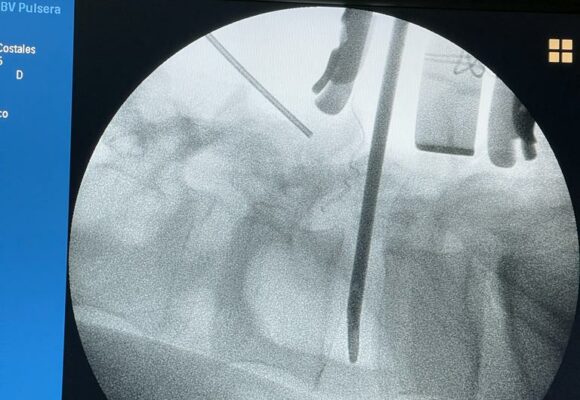

Cirugías de columna con equipos de última generación

Soy Neurocirujano, orientado a la neurocirugía de emergencia, lesiones intracerebrales y patologías de columna vertebral, tanto en adultos como en niños; conocimiento del manejo de equipos de microcirugía, endoscopía, estereotaxia, neuronavegación, imagenología.